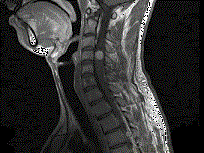

问题 男,24岁,颈部疼痛,并右上肢麻木,以手部明显,请根据所提供图像,选择最可能的诊断 ( )

选项 A、(颈4~5)血管母细胞瘤 B、(颈4~5)胶质瘤 C、(颈4~5)脊膜瘤 D、(颈4~5)海绵状血管瘤 E、(颈4~5)神经鞘瘤

答案 E